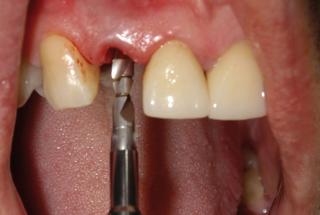

Clinical cases

MPI closely monitors clinical cases in the market to ensure their correct functioning and successful outcome.